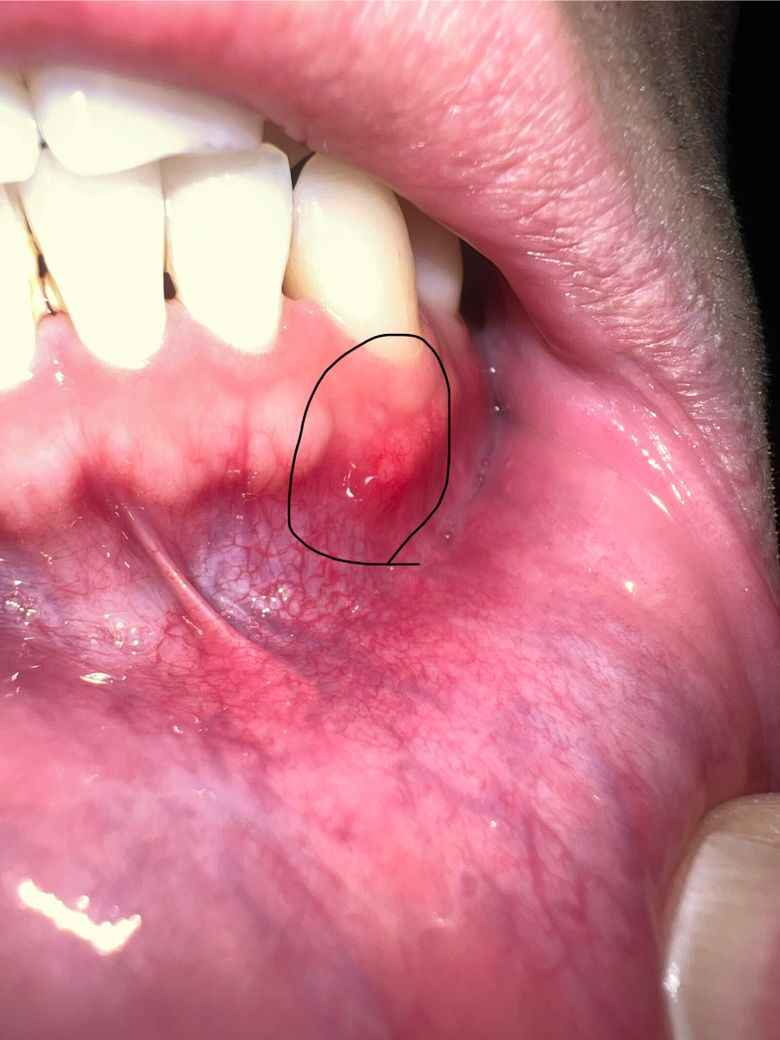

잇몸에 뾰루지 같은데 낫던데 염증생긴겅가요?

잇몸에 뭔가 불편감이 있어서 보니까 뾰루지 같은게 낫던데 염증난건가요

가만히 있으면 통증이나 뭐 그런게 없어서 잘모르겠는데 건들면 통증이 좀 있네요

단순 구내염이 생긴 것으로 보이지만 1주일 정도 지켜보시고 사라지지 않으면 치과 가보시는 게 좋습니다.

염증은 아닌거 같고 잇몸부위가 자극을 받아서 물집이 잡힌거 같습니다. 통즈잉 없다면 크게 걱정하지 않으셔도 됩니다.

현재 잇몸에 염증이 있어 보이며,치석이 있는 경우 잇몸을 자극하여 잇몸에 염증을 유발할수 있습니다.

통증이 더 심해지거나, 해당 부위가 붓거나, 고름이 나오는 경우 치과에 방문하여 상태를 확인하고, 스케일링 및 염증치료를 받길 권합니다.